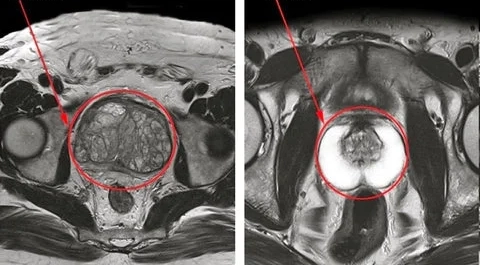

Olha só, minha próstata está saudável em apenas algumas semanas de uso! Meus exames que acabei de receber. Estou impressionado!!!